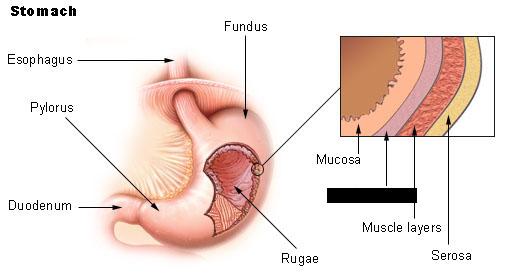

Duodenum

Esophagus

Fundus (of stomach)

Body (of stomach)

Cardia (of stomach)

Pylorus (of stomach)

Pyloric Sphincter

Rugae (of stomach)

Mucosa

Serosa

Gastroesophageal sphincter